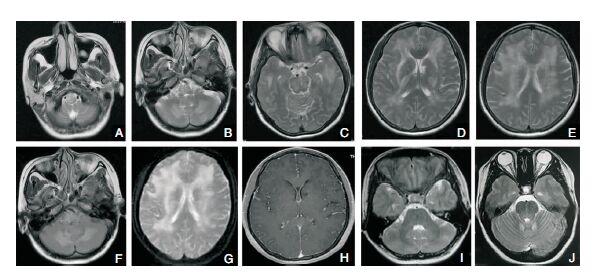

1.4 影像学检查6例患者均行头部MRI平扫增强+MRV检查,均表现为双侧对称性病灶,累及脑干、小脑、枕叶、颞叶、侧脑室旁白质1例;累及脑干、小脑、枕叶3例;累及枕叶、顶叶2例。均表现为长T1长T2信号,DWI呈低信号,flair呈高信号,均无强化,MRV均未见异常。见图 1A~图 1H。

| 图 1 38岁女性患者(头痛半年,加重伴恶心呕吐2月入院。既往高血压病史,最高190/126 mmHg,未服降压药,继发慢性肾病病史,未服药。长期使用煤火卖早餐)入院后MRI图像。A-E:T2WI成像示脑干、小脑、颞叶、侧脑室旁白质对侧性高信号病灶;F:Flair成像病灶呈高信号;G:ADC成像呈高信号;H:病灶无强化;图I-J:治疗2周后复查T2加权像,病灶明显缩小。 |

6例患者入院后初步诊断中毒性脑病及RPLS均有可能,3例患者给予地塞米松、控制血压、降颅压、抗癫痫等治疗5 d,血压控制不佳,患者症状加重,后停用激素,予控制血压、抗癫痫等对症治疗,患者症状明显好转;另3例患者入院后即予控制血压、降颅压等治疗,病情较快恢复。6例患者经控制血压等治疗后临床症状均逐渐消失,随访无后遗症。见图 1I和图 1J。